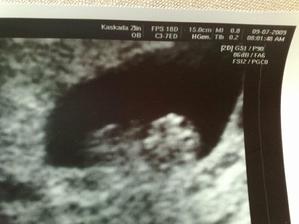

Od poslední operace jsem užívala Utrogestan po něm mi nebylo moc dobře, tak se nasadila Provera.Po ní mám stejně MS nepravidelnou.Koncem května jsme se rozhodli navštívit Car.Chtěli jsme do Zlína, pač to máme blíž, ale moje pojišťovna s nimi nemá slouvu, takže nic.Takže jsme hledali a našli si v Olomouci Fertimed.Objednali jsme se na konzultaci 2.7.2008.Konzultace proběhla bez problému, jen vyšetření, které proběhlo před přítelem bylo pro něj trochu překvapením.Příteli udělali SPG kde zjistily že je v pořadku.Posléze nám byli zjištěny Ureoplazmata, tak jsme s přítelem zobali ATB. Nebylo nám ani jednomu znich dobře. A měli jsme zakázáno snažilkování. 20.8.2008 jsem měla jít na svou první IUI, ale bylo mi zjištěno, že nemám ovulaci.Tak s toho sešlo.9.9.2008 jsem měla vyšetření průchodnosti.12.9.2008 jsem šla na KO a na výsledky.Vše je ok, vše mám průchodný i po všech operacích a ureoplazmatech.A snažilkování opět zakázáno kvůli zahojení.Poprvé mi byly dány stimulace Clostilbegyt.Tak teď už jen čekám na mrchu.Mrcha dorazila 3.10. takže opět smůla,7.10. začínám zobat Clostilbegyt.Po sexíku po něm trochu špinim, ale je to možná ještě brzy kvůli tomu vyšetření průchodnosti. 13.10. jedu do Car na KO hm tak jsem zvědavá jak to na mě zapůsobilo.Uvidíme co budu mít v bříšku 🙂) KO dopadla dobře mám 4 vajíčka o velikosti 1.4cm a sliznici 5.5cm. 17.10.08 v 13hod máme první inseminaci.Po píchnutí pregnylu mi není dobře a ještě k tomu ten divný klobouček co zavádějí.19.10. kontrola a druhá inseminace.29.10. Kontrola v CAr a nalezena další cysta.Další cyklus tedy proběhne bez Clostíku.19.11. kontrola máme ovulaci a 2 folikuly.24.11. třetí inseminace opět je mi špatně po pregnylu a ten klobouček hrůza 26.11. čtvrtá inseminace opět je mi špatně po pregnylu, odebrána krev na tumorové markry,štítnou žlázu a cytologie.5.12. kontrola není nic vidět, krev v pořádku aspoň se nemusím bát že mám v sobě rakovinové buňky,štítná žláza též v pořádku.Cytologie bude po Vánocích.Přes Vánoce nepracují tudíž se budeme snažilkovat doma.Přes Vánoce jsem si zkoušela porvé udělat ovulační testy.Testy mi vycházely // jeden mi vyšel i s /// což bylo tedy opravdu divné.5.1.09 jsem si udělala poslední ovu test s// nu jenže 6.1.09 jsem dostala pěkně silnou MS.12.1.09 jsem byla u své obvoní dr, která mi vzala krev a moč.13.1.09 jsem byla u své gynekoložky a ta mi řekla že jsem měla opět cystu která byla už prasklá.Moje obvodní lékařka mi řekla ,moč je v pořádku,ale v krvi mi chybí červené barvivo v červených krvinkách.Tak jsem si koupila železo s kyselinou listovou.21.1.kontrola v CAR řekli mi že mám 2folikuly, odmítla jsem IVF, a objednala se do FN Olomouc (10.března 11:45) k dr. Dostálovy, výsledky z cytologie dopadly dobře. 10.3. první poradna u doc.Dostála, vše probíhalo v pořádku, zatím jsme jen dotsali papíry na IUI. 23.3. 13dc sliznice 10mm, ovarium vlevo 14+PCO, ovarium vpravo 17mm, 25.3.-27.3. plánovaný styk. 21.4.09 13dc sliznice 10,3mm, vpravo 19x26mm folikl, dnes IUI, následující den plánovaný styk,zavádění Utrogestanu po 8dní. 13.5. poradna s doc. Dostálem, výsledky horm. profilu ok, spg ok, domluva na IVF ( srpen 09 ), dostala jsem veškeré léky a poučení. 18.5. 13dc sliznice 11mm, ovarium vlevo 17mm, vpravo nic, 19.-20.5.09 plánovaný styk.21.5. UTZ sliznice 7,4mm, ovaria 0, 1.6.09 HCG 103,9. 18.6.09 UTZ 6tt embryo s pravidelnou akcí srdeční. 25.6.09 UTZ 7tt vše ok. 9.7.09 UTZ 9tt těhu průkazka. 3.8.09 Prediko UTZ 13tt vše ok jen nemáme změřenou nosní kůstku. 6.8.09 13tt kontrola, 26.8.09 16tt kontrola 1,5kg, 10.9.09 18+1 kontrola 0,5kg, 24.9.09 20+1 kontrola první pohyby 2,5kg, 25.9.09 Prediko UTZ 20+2, 15.10.09 23+1 1,5kg, 2.11.09 test na cukrovku už nikdy v životě!, dietu nedržím ale musím chodit na ko, 5.11.09 26+1 2kg,